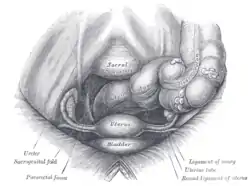

Female pelvis and its contents, seen from above and in front. (Lumps of fat visible at right.) | |